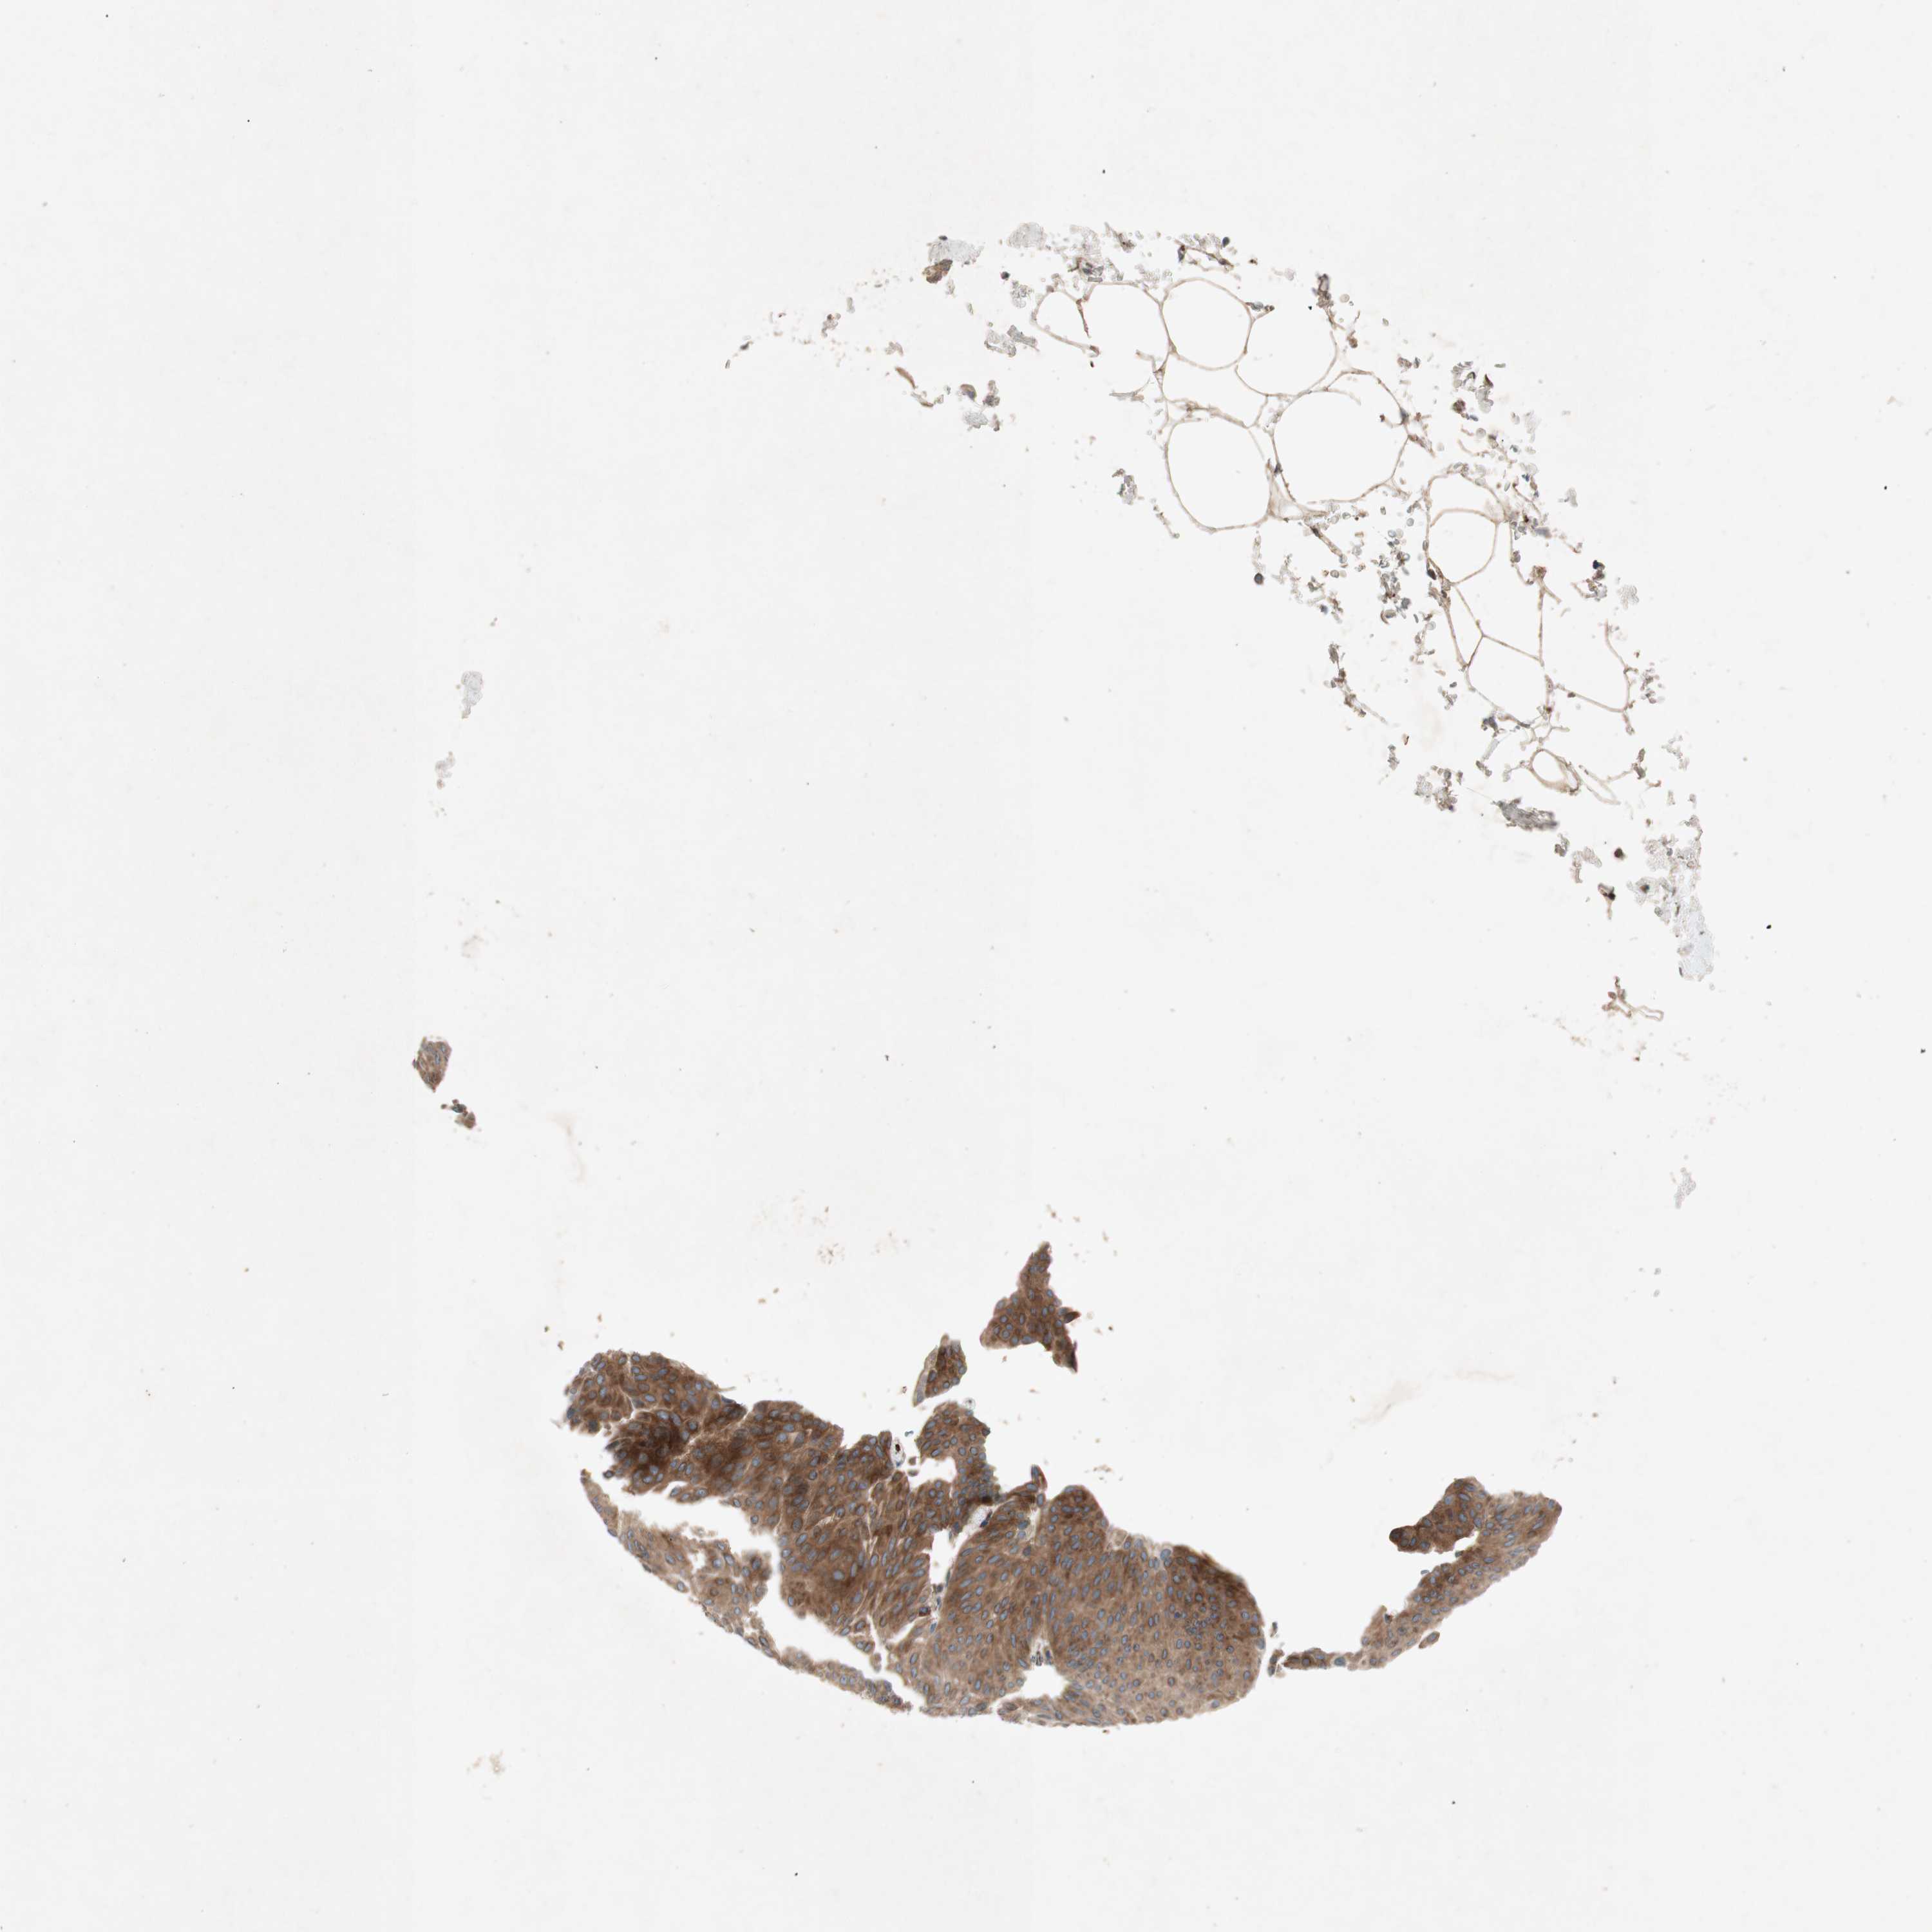

UROTHELIAL CANCER - Protein expressioni

A mouse-over function shows sample information and annotation data. Click on an image to view it in a full screen mode. Samples can be filtered based on level of antibody staining by selecting one or several of the following categories: high, medium, low and not detected. The assay and annotation is described here.

Note that samples used for immunohistochemistry by the Human Protein Atlas do not correspond to samples in the TCGA dataset.

Antibody stainingi

Antibody staining in the annotated cell types in the current human tissue is reported as not detected, low, medium, or high, based on conventional immunohistochemistry profiling in selected tissues. This score is based on the combination of the staining intensity and fraction of stained cells.

Each image is clickable and will lead to virtual microscopy that enables deeper exploration of all samples and also displays staining intensity scores, fraction scores and subcellular localization as well as patient and tissue information for each sample.

Antibody HPA003187

Staining

High

Medium

Low

Not detected

Intensity

Strong

Moderate

Weak

Negative

Quantity

>75%

75%-25%

<25%

None

Location

Nuclear

Cytoplasmic/membranous

Cytoplasmic/membranous,nuclear

Urothelial carcinoma, Low grade

Urothelial carcinoma, High grade